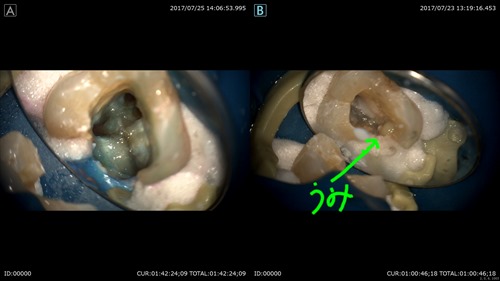

術前が右。術後が左です。